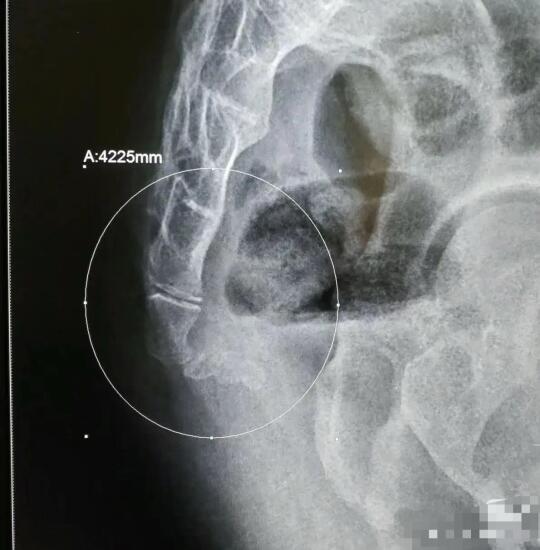

有很多人不能久坐 坐久了就会出现尾椎疼 其实尾椎疼有三个原因 第一像图二尾椎骨折有勾进去 坐着非常容易尾椎受力 第二像图三尾椎比较长的这种 坐着的时候如果不注意也容易压到尾椎 第三是骨盆后倾 骨盆后倾的时候支撑点在坐骨的后侧 这时候尾椎也容易被压到 当然第一二种情况往往会伴有骨盆后倾 前段时间有客户咨询我说坐着时候尾椎会疼 我就给她推荐无极骨盆矫正椅 她收到产品一试坐 感觉特别舒服再也不用压迫尾椎了 她是知道自己骨盆后倾导致的尾椎疼 并且又下单买了一把无极骨盆矫正椅